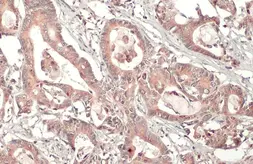

Images